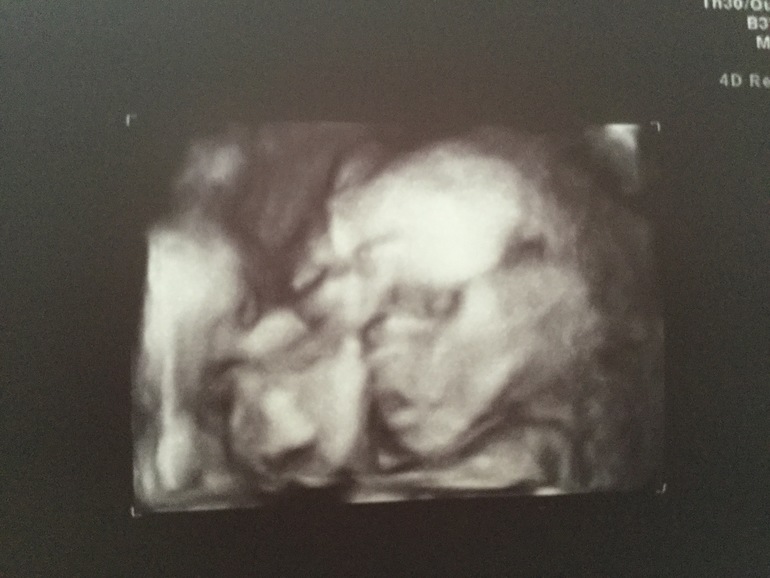

22ая уже! Были на узи )

ЭкваторДни стремительно летят. Неделю назад был Экватор!! Сегодня пошла 22ая неделя, как я жду нашу дочку.

Купили первую одёжку! Приглашаю под кат посмотреть бодик для девочки, фотографии с узи и мой животик, какой он сегодня с утра )

Вот такая она сейчас!! А вот фото, какая была 3 недели назад